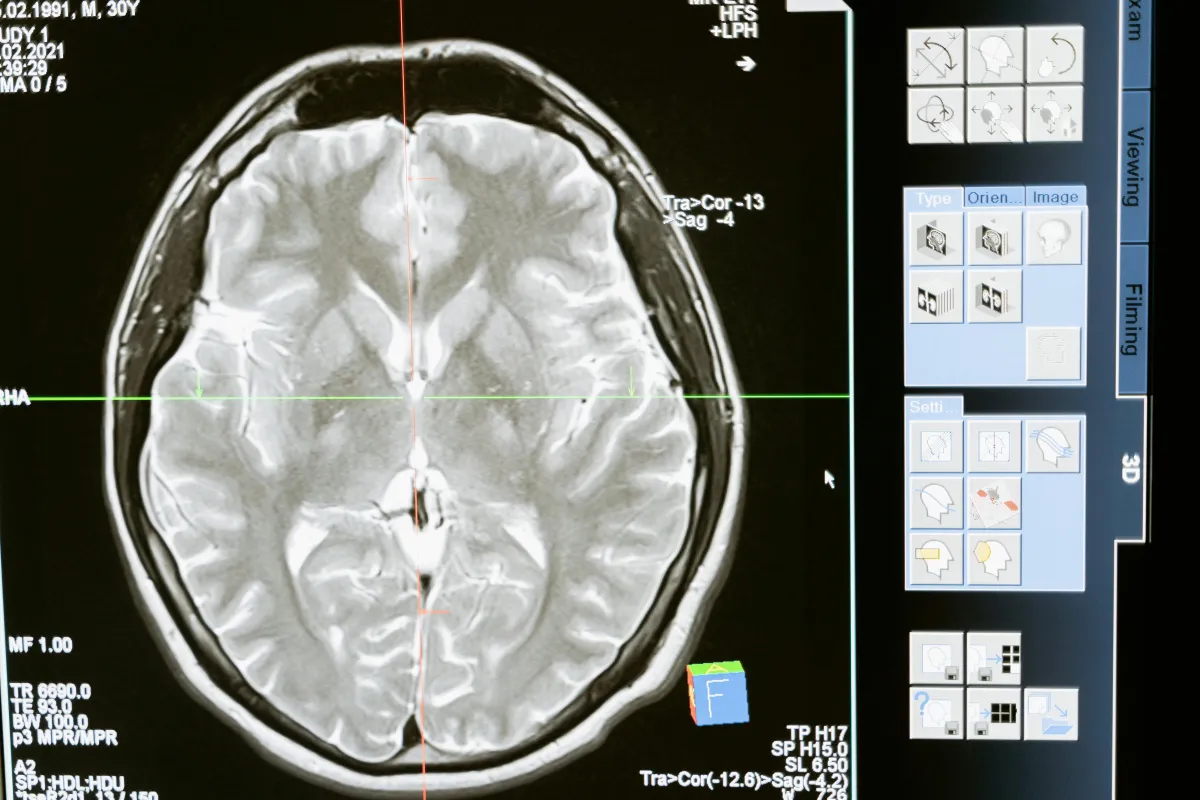

Concussions and traumatic brain injuries (TBIs) can have lasting effects on cognitive function, memory, and overall well-being. Whether caused by sports, accidents, or other impacts, these injuries disrupt the brain’s ability to heal efficiently. Hyperbaric Oxygen Therapy (HBOT) is a powerful, research-backed treatment that enhances oxygen delivery to the brain, reducing inflammation, promoting neural repair, and accelerating recovery. Discover how HBOT can support your healing journey.

A concussion is a mild traumatic brain injury (mTBI) caused by a blow to the head or sudden jolt. Concussions disrupt normal brain function and may lead to headaches, dizziness, memory loss, and emotional instability. While symptoms typically resolve within weeks, some individuals experience prolonged issues known as post-concussion syndrome (PCS).

Traumatic Brain Injury (TBI) occurs when an external force injures the brain, commonly due to falls, accidents, or sports injuries. TBIs range from mild (concussions) to severe and can result in long-term cognitive, emotional, and physical impairments. Recovery often involves physical therapy, cognitive rehabilitation, and other supportive therapies. HBOT is increasingly recognized for its ability to accelerate healing and improve neurological function.